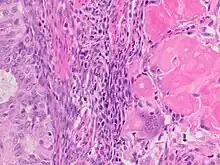

Endometrial adenocarcinoma with necrotic ghost cells of keratinocytes at right in image, leaving pink keratin and clear spaces at the prior locations of the nuclei.

A ghost cell is an enlarged eosinophilic epithelial cell with eosinophilic cytoplasm but without a nucleus.

The ghost cells indicate coagulative necrosis where there is cell death but retainment of cellular architecture. In histologic sections ghost cells are those which appear as shadow cells. They are dead cells. For example, in peripheral blood smear preparations, the RBCs are lysed and appear as ghost cells.